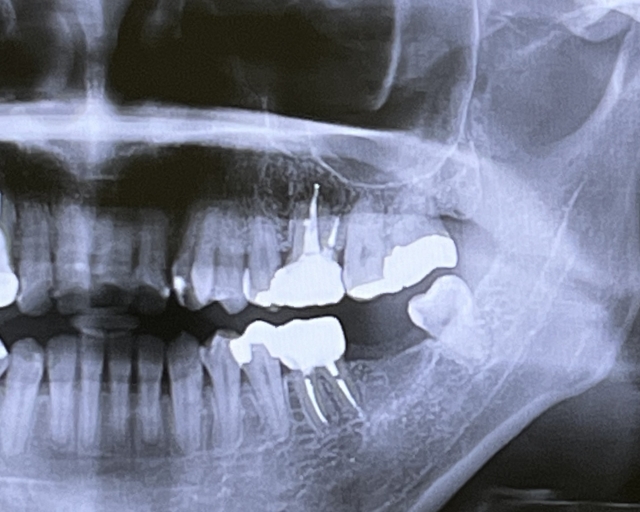

歯の神経のレントゲン

根管治療する際には、レントゲンなどでその見えない部分の形態を確認しながら慎重に進めていきます。ですが、レントゲン写真も2次元(平面)でしかないため完全に形態を把握することはできません。難しい根管の場合にはCTという3次元(立体)のレントゲンを撮影し、根管の形態を立体的に見て治療を進めていきます。